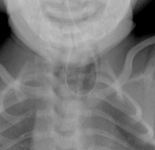

Avaliação da cianose neonatal

Taquipneia transitória do neonato (síndrome do desconforto respiratório tipo 2): estrias peri-hilares e fluido na fissura horizontal à direita

Do acervo de Ponthenkandath Sasidharan, MD; usado com permissão